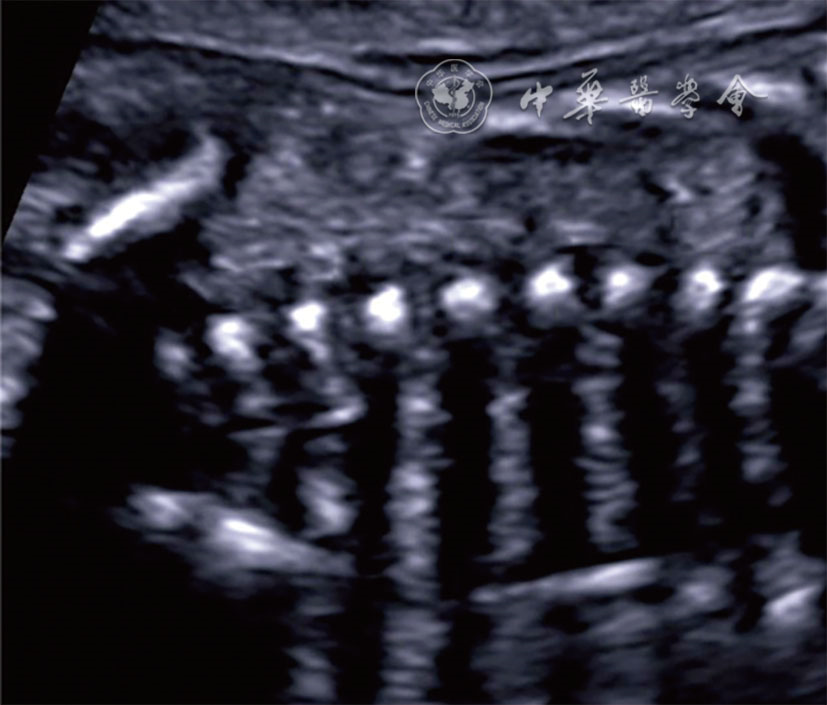

图23 脊柱横切面超声图像 注:VA为椎弓;VB为椎体;SC为脊髓